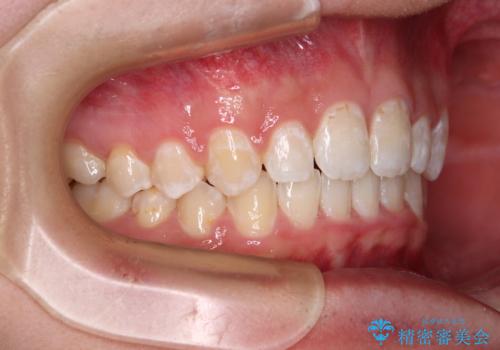

下顎前歯が全て隠れてしまうほどの深い咬合で、左右の奥歯は1歯対1歯で咬み合う状態でした。

前方に移動している上顎臼歯を補助装置にて遠心移動させることで1歯対2歯の臼歯咬合を目指し、同時に深い咬合を改善していくこととしました。